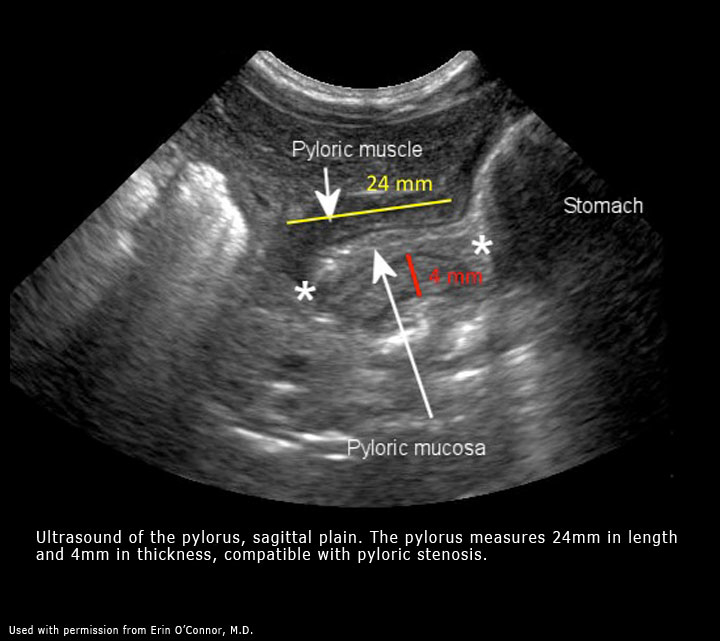

Transverse view of pyloric stenosis

On axial you see the classic donut sign